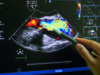

This is according to a panel of experts who have reviewed current barriers to more widespread usage of imaging technologies—including intravascular ultrasound (IVUS) and optical coherence tomography (OCT)—which remains low despite latest clinical practice guidelines favouring their use in specific clinical and anatomical scenarios.

Though the use of intravascular imaging is seen as a relatively new innovation in the field of coronary interventions, Escaned et al’s paper identifies that these technologies have been in circulation for several decades, noting that in Japan, for example, where as many as 84.4% of percutaneous coronary intervention (PCI) procedures involve the use of IVUS or OCT in some form, the use of intracoronary imaging has been relatively well established since the mid-1990s.